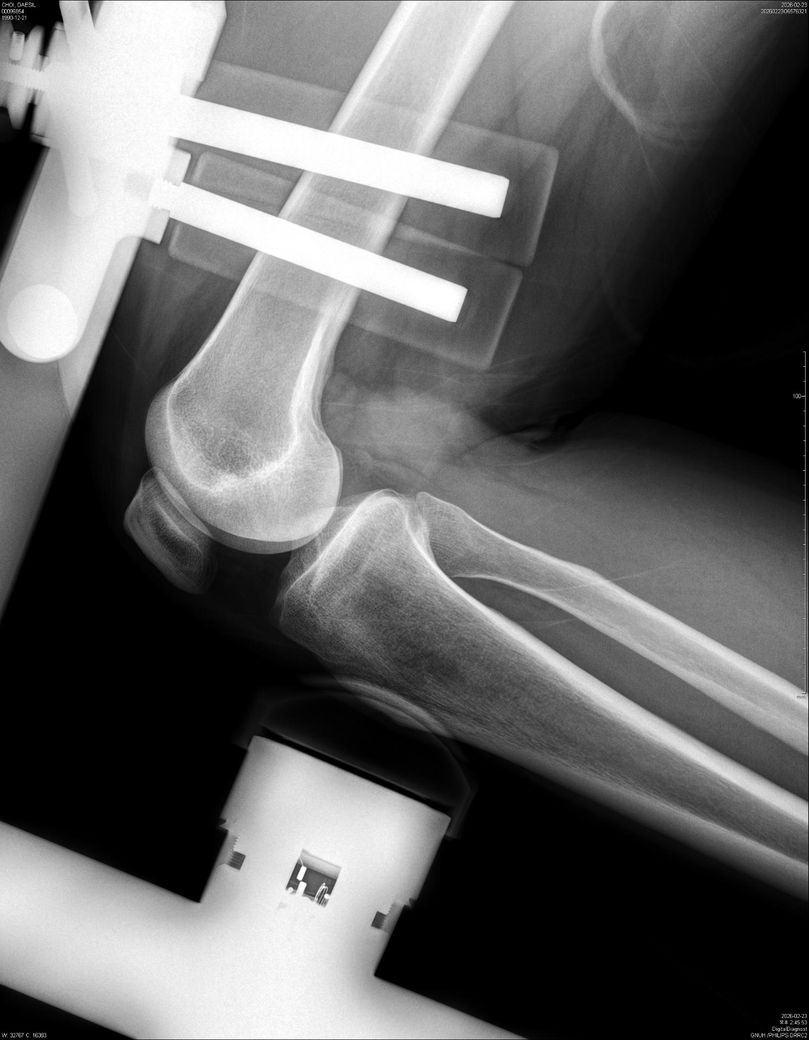

• 3번 째 사진

이 X-ray는 뼈 정렬·고정물 위치만 볼 수 있어, “무릎 동요도(십자인대 안정성)”는 판단할 수 없습니다.

동요도는 Lachman, Pivot shift 같은 이학적 검사나 MRI로 확인해야 합니다.

단순 엑스레이 사진만으로는 무릎 동요도를 측정하기 어렵습니다.

전문 장비를 이용한 검사나 스트레스 엑스레이등을 이용한 평가를 통해 확인하시는 것을 추천드립니다.